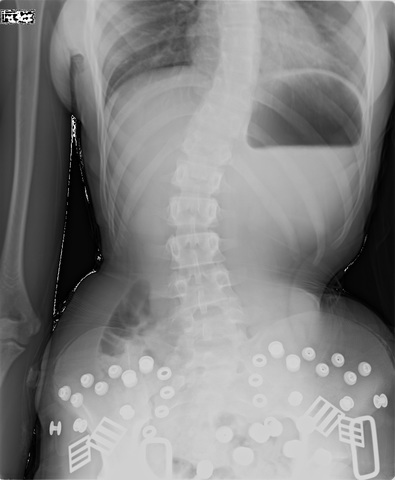

Brianna complained of back pain, and I noticed that her spine was twisted.

Spoke on phone and emailed X-rays. Dr. Pappas said she would be an excellent candidate with approximately 18 degree curve. Based in Chicago with the nearest office in Phoenix, the travel, costs and doctor visits were too financially burdening.

Was told that Brianna had scoliosis and treatment and therapy would be around $5000.00 for the first 3 months.(see posture screening via email)

Was told that Brianna had approximately 12 degree curve and thermal scan and EMG scan was performed as well as various assessments. Weekly adjustments of minimum 2/week was recommended at an affordable rate. Dr. Wise was thorough in his assessment and test in knowledge of pediatric scoliosis. I felt confident for his care with Brianna. (see documents)

Dr. Pappas had several x-rays requested (see email from the 27th of June 2016)) and they were taken at Align Chiropractic with Dr. Durso.

Dr. Pappas emailed me to discontinue brace and call him immediately. (see email)

Told by Dr. Pappas that the brace was placed on the incorrect side and that her spine had worsened (see phone record and email)